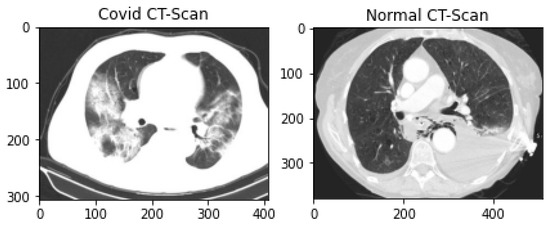

The public CT scan dataset for pandemic diagnosis and classification used in this research is SARS-CoV-2 CT-scan, prepared by Soares et al. These data were collected from hospitals in Sao Paulo, Brazil, and are publicly available on Kaggle Repository [55]. This dataset contains 2482 CT scans (1252 infected lung CT-scan images and 1230 non-infected lung scan images). The dataset consists of CT scans of 62 male patients and 58 female patients. This dataset comprises 2D slices of CT scans with no standard-size images. The smallest image in the dataset is 104 × 153 while the largest one is 484 × 416. The samples of both normal and pandemic-infected CT scans are shown in Figure 3.

Figure 3.

Covid-infected and Normal Lung CT scan Data Samples.